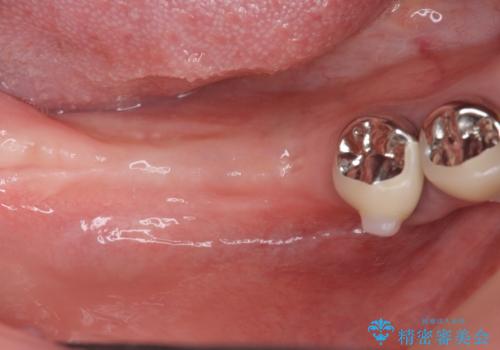

遊離歯肉移植術を伴うインプラント治療

- 虫歯が多く、全体的な歯の検診を希望され当院に来院されました。

X線写真検査より、クラウンや銀歯の下で歯に大きな虫歯が発生し、抜歯を余儀なくされる状況でした。

虫歯に伴い歯槽骨の吸収も見られたので造骨後、インプラントを用いて咬合機能を回復します。

また、機能後のインプラント周囲の清掃性を高めるため遊離歯肉移植術を行っています。